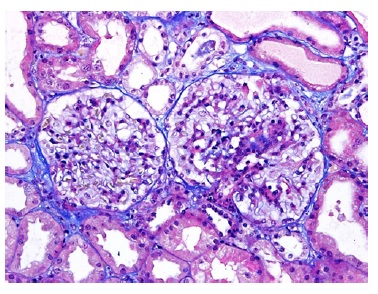

A kidney biopsy was performed, showing on light microscopy 22 glomeruli (Figure 1), one of them with global sclerosis, and five with segmental sclerosis (Figure 2). The remaining glomeruli showed swollen podocytes and segmental mesangial proliferation (Figure 2). Immunofluorescence identified mesangial and granular staining of IgA, C3c, C1q, IgM and IgG. Electron microscopy showed diffuse FPE, with only scant immune deposits confined to the mesangium (Figure 3 and Figure 44).

Figure 2: TE 200x. Glomeruli with segmental mesangial proliferation, segmental sclerosis and swollen podocytes.